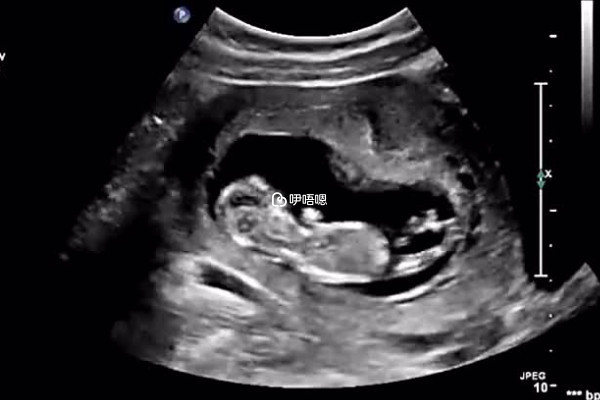

三維彩超單子看生男生女主要是看寶寶的生殖器官,因為懷孕24周左右的時間,寶寶的生殖器官基本上已經發育成熟,可以從三維彩超的單子上比較直觀的看出胎兒的性別,但是由於胎兒體位的問題,有時候並不能直接看到,用單子上是m開頭是男孩,如果是f開頭那就是女孩的這種判斷方法不準確。

四維彩超是孕檢排畸做的一項檢查,並不是用來判斷生男生女的,國家規定了任何醫療機構及個人都不得做胎兒性別鑑定,沒有醫學指徵的情況下,現在網上流傳了很多通過四維彩超判斷生男生女的判斷方法,其實都不準確,以下是通過四維彩超看生男生女的方法: